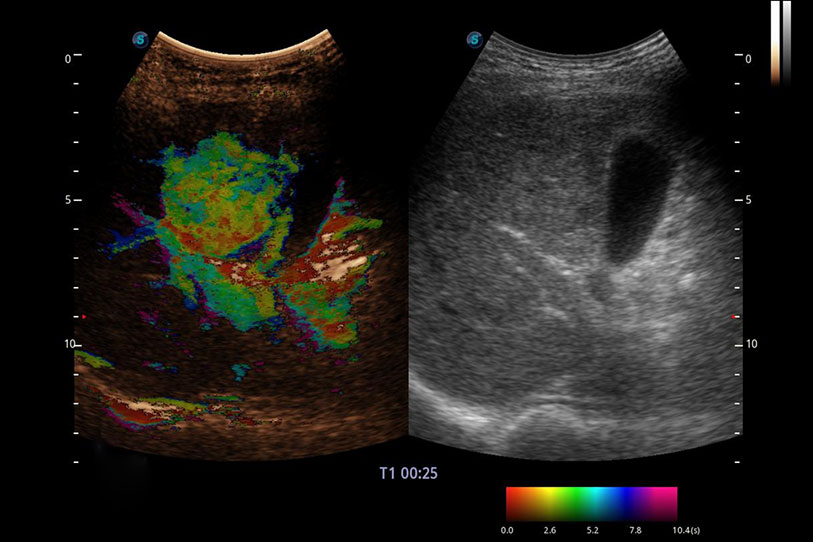

采用紅、橙、黃、綠、青、藍(lán)、紫這七種肉眼最為敏感的色彩,直觀地顯示組織內(nèi)血流灌注的時(shí)間先后信息,更精準(zhǔn)捕捉血流灌注走行細(xì)節(jié)。